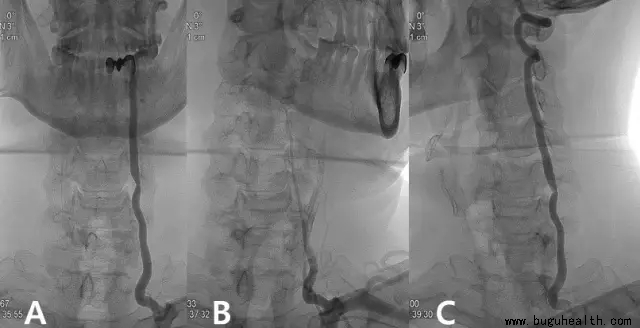

Case 1

图A:显示C5-6水平左侧椎动脉狭窄;

图B:患者头部向左侧旋转45°后DSA显示左侧椎动脉近完全闭塞;

图C:患者头转向右侧,左侧椎动脉血流恢复。